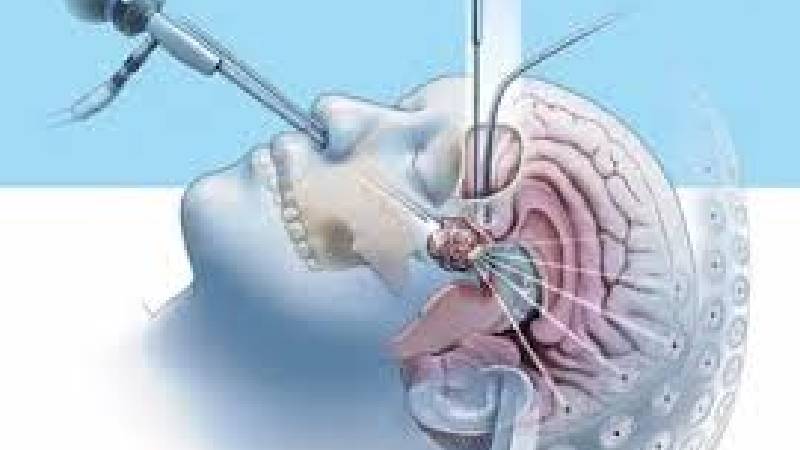

Our Speciality

Vast Experience Over Last 29 Years

I recently had a surgery here for my sinus issue. Had a really good experience here. Dr. Pradeep has been very supportive and ensured my surgery is done with all the precautions. His guidance and treatment has helped me in my recovery. The staff of the hospital is hands on really good. They ensure that the patient does not face any discomfort and are available for any help required. I would recommend Dr. Pradeep & Gadiwan hospital for all kinds of ENT related treatments and surgeries. You will be in safe hands here and will taken good care of. Thankyou to Dr. Pradeep & Gadiwan hospital team 😊